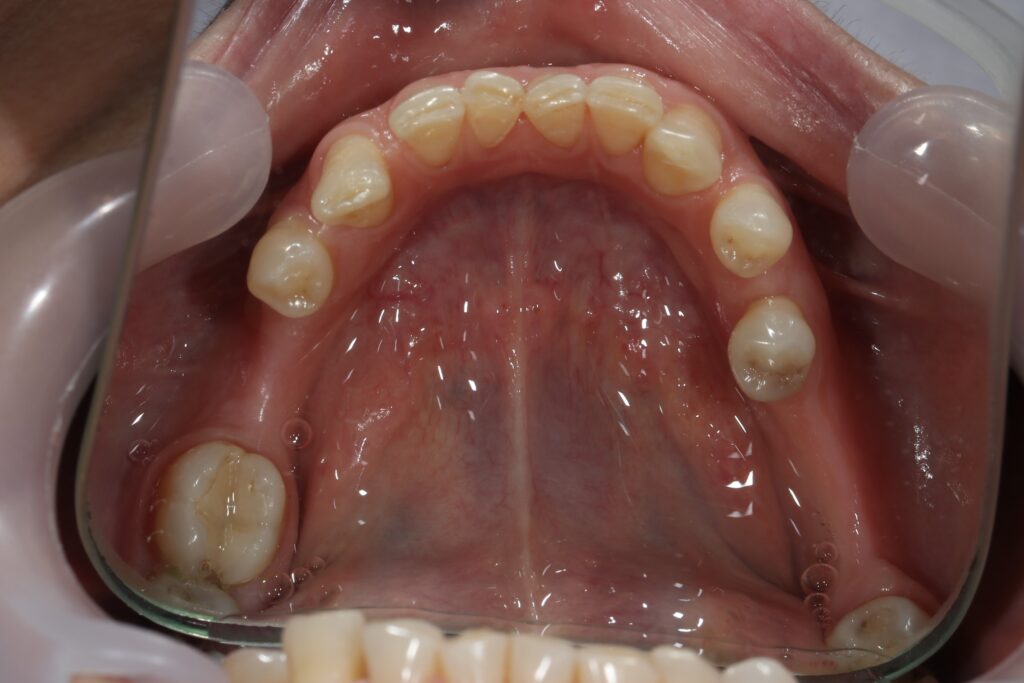

Ситуация до лечения

Пациентка 39 лет была направлена стоматологом-ортопедом для ортодонтической подготовки перед протезированием.

Из-за множественных давних удалений жевательных зубов, произошла деформация зубных рядов, зубы разъехались в область удаленных, что затрудняло протезирование в момент обращения к ортопеду.

Так же можно отметить сильное снижение высоты прикуса (верхние зубы на 100% перекрывали нижние, что вызывало хроническую травму десны), а также повышенную стираемость твердых тканей зубов,

что является следствием повышенной нагрузки, которую много лет испытывали передние зубы, в связи с отсутствием жевательных зубов.

пациент до брекетов